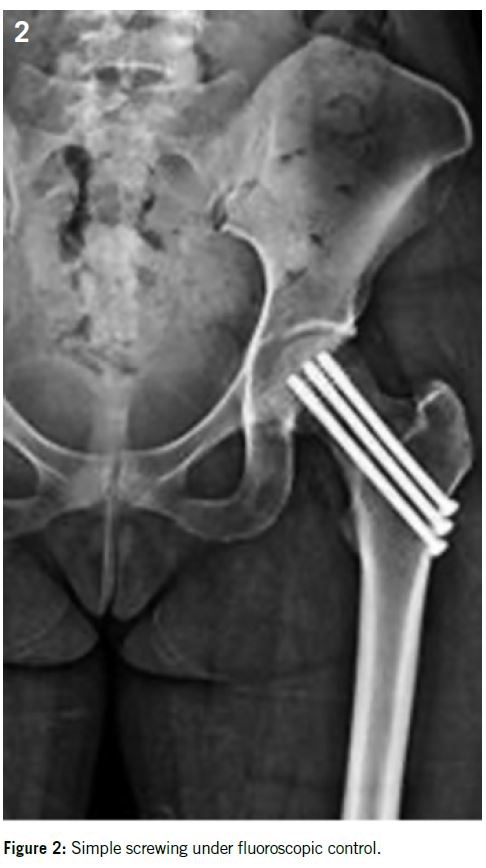

Fracture of the femoral neck: 5% of all BSF. It occurs more frequently in young sportswomen, runners, and military recruits2,24. It can be influenced by certain risk factors such as rapid muscle mass loss combined with a high level of training, decreased femoral bone mass density, gluteus medius weakness, coxa valga, or femoro-acetabular impingement9,18,26,32.

Patients usually complain of hip, inguinal or proximal thigh pain. Pain may be provoked by a single leg hop.

X-rays are positive in only 15% of cases in the early stages, so MRI is the imaging of choice showing the fracture at the superior cortex (tension side) or inferior cortex (compression side) associated with bone marrow edema.

Superior cortex fractures are particularly at risk of displacement so simple fixation by percutaneous screwing can be considered. Generally, three 6.5 mm diameter cancellous screws are placed under fluoroscopic control. In more advanced cases or in heavier or overweight patients, a more sturdy fixation such as a dynamic hip screw may be proposed14 (Figures 2 and 3).